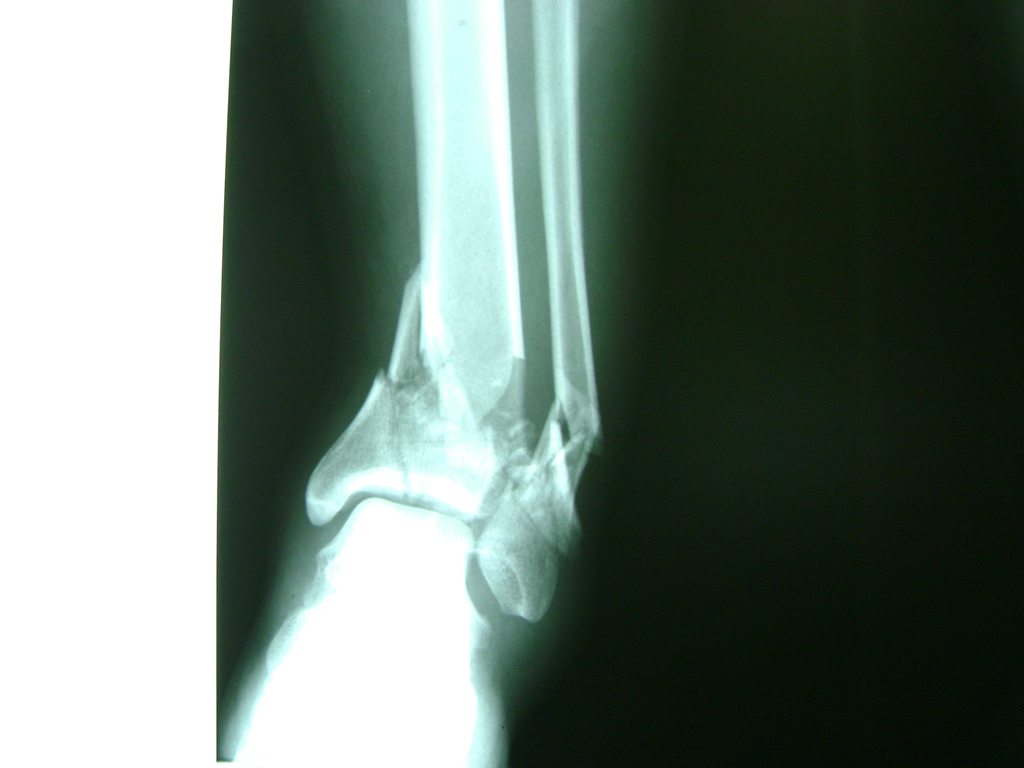

Una fractura de tobillo es la rotura de uno o más de los huesos del tobillo. Estas fracturas pueden ser:

- Completas (el hueso está perforado y está en 2 partes).

- Producirse en uno o ambos lados del tobillo.

- Los extremos de los huesos están desalineados entre sí (desplazados).

- La fractura se extiende hasta la articulación del tobillo (fractura intra-articular).